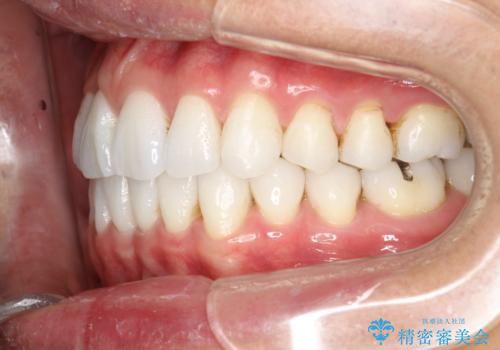

インビザライン終了時のPMTC

PMTC60分1万円+tax(保険適応外)を行いました。

インビザライン矯正治療は、歯にアタッチメント(歯を動かすための突起物)をつけます。そのため、矯正治療が終了し、アタッチメントを外すと着色が目立つことがあります。矯正治療の終了のタイミングではクリーニングを行い、着色の除去や歯と歯の間・歯と歯肉との境目などのケアをしっかりすることをおすすめしています。